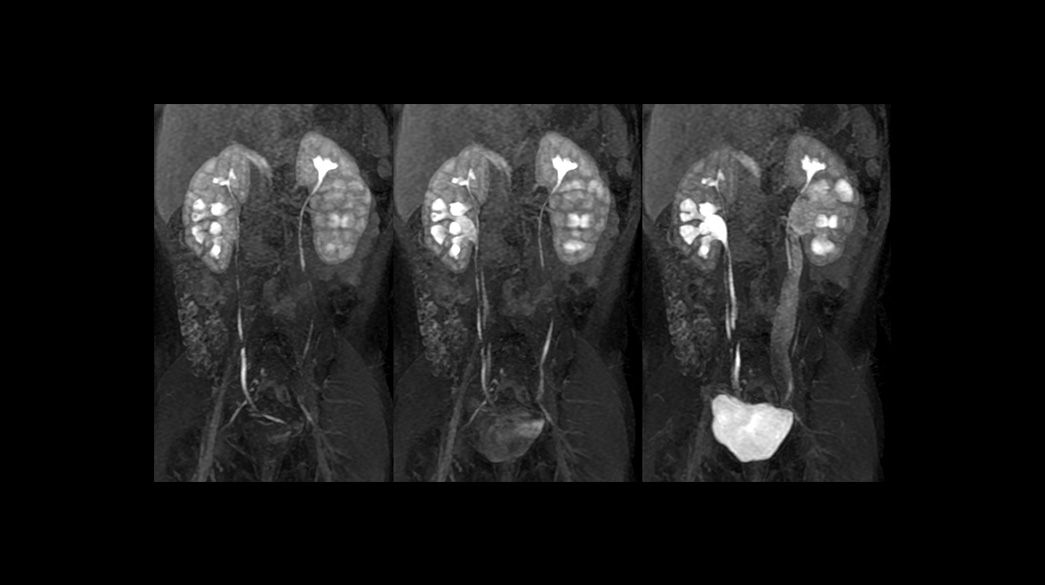

Pediatric MRI imaging applications

Access and productivity